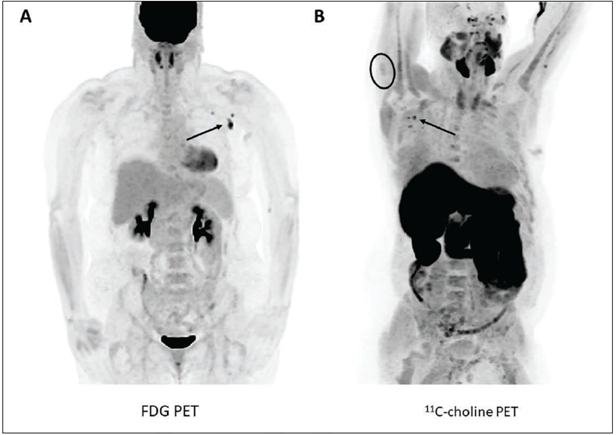

This photo gallery shows the variety of radiological presentations of COVID-19 (SARS-CoV-2) in medical imaging, including computed tomography (CT), radiograph X-rays, ultrasound, echocardiograms and magnetic resonance imaging (MRI). The radiology images show examples of typical COVID pneumonia in the lungs and the numerous complications the virus causes in the body in multiple organs, including the brain, kidneys, heart, abdomen and vascular system.

Ultrasound, especially hand-held ultrasound imaging devices, have become a primary imaging modality for novel coronavirus because of the ease to bag the device and sterilize it after use. CT and mobile X-ray systems are also used as front-line imaging systems for COVID-positive or suspected COVID patients.